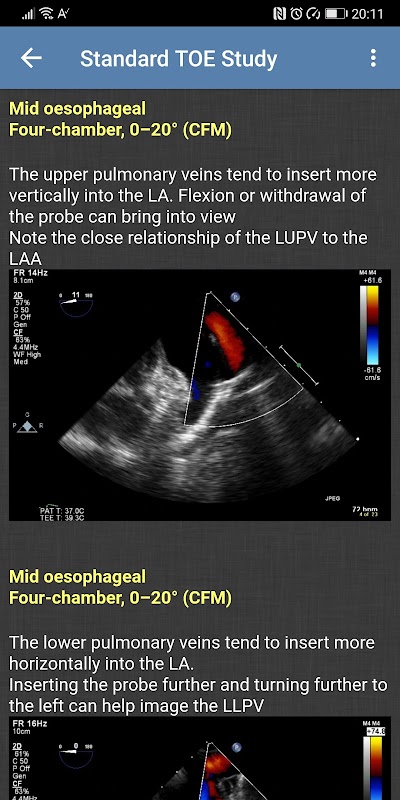

- Estudio TOE estándar